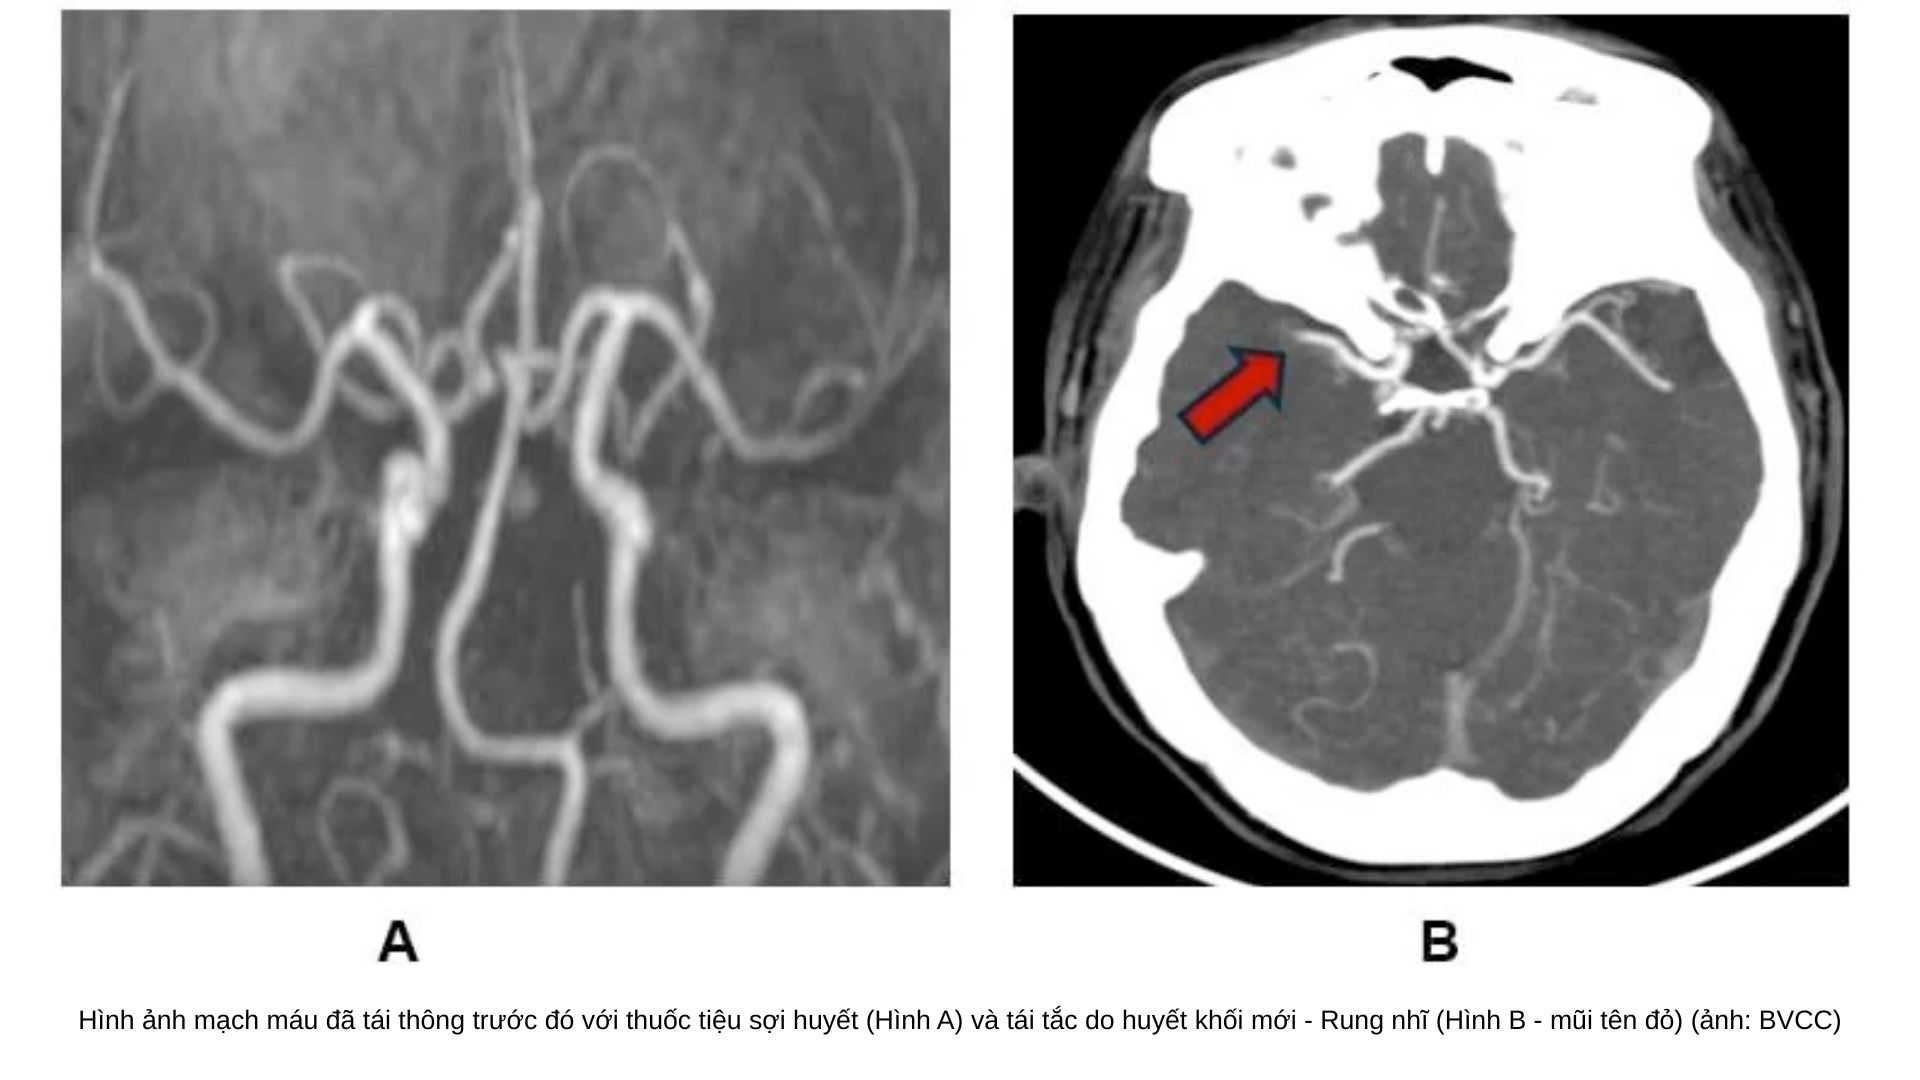

Cấp cứu thành công ca đột quỵ tái phát nhờ tái thông mạch máu khẩn cấp

Ngày 17/6/2025, Bệnh viện Nhân dân 115 (TPHCM) cho biết, đơn vị vừa điều trị thành công trường hợp bệnh nhân nữ 57 tuổi bị đột quỵ tái phát nguy kịch chỉ trong vòng chưa đầy 48 giờ.